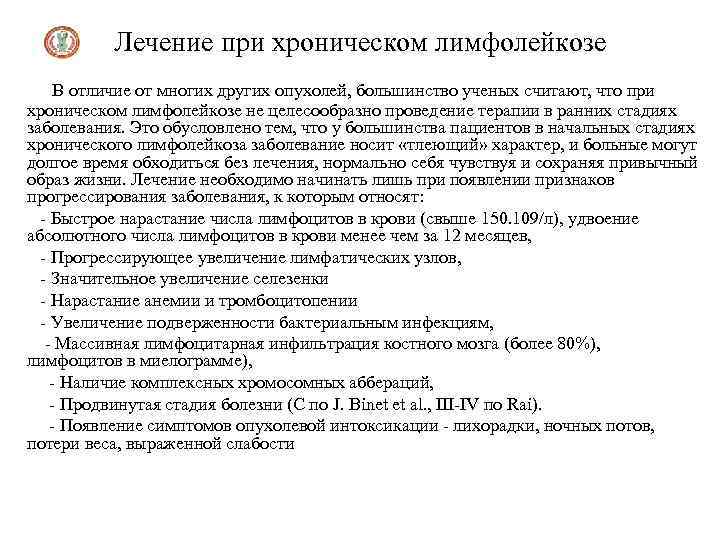

Лечение при хроническом лимфолейкозе В отличие от многих других опухолей, большинство ученых считают, что при хроническом лимфолейкозе не целесообразно проведение терапии в ранних стадиях заболевания. Это обусловлено тем, что у большинства пациентов в начальных стадиях хронического лимфолейкоза заболевание носит «тлеющий» характер, и больные могут долгое время обходиться без лечения, нормально себя чувствуя и сохраняя привычный образ жизни. Лечение необходимо начинать лишь при появлении признаков прогрессирования заболевания, к которым относят: - Быстрое нарастание числа лимфоцитов в крови (свыше 150. 109/л), удвоение абсолютного числа лимфоцитов в крови менее чем за 12 месяцев, - Прогрессирующее увеличение лимфатических узлов, - Значительное увеличение селезенки - Нарастание анемии и тромбоцитопении - Увеличение подверженности бактериальным инфекциям, - Массивная лимфоцитарная инфильтрация костного мозга (более 80%), лимфоцитов в миелограмме), - Наличие комплексных хромосомных аббераций, - Продвинутая стадия болезни (С по J. Binet еt al. , III-IV по Rai). - Появление симптомов опухолевой интоксикации - лихорадки, ночных потов, потери веса, выраженной слабости